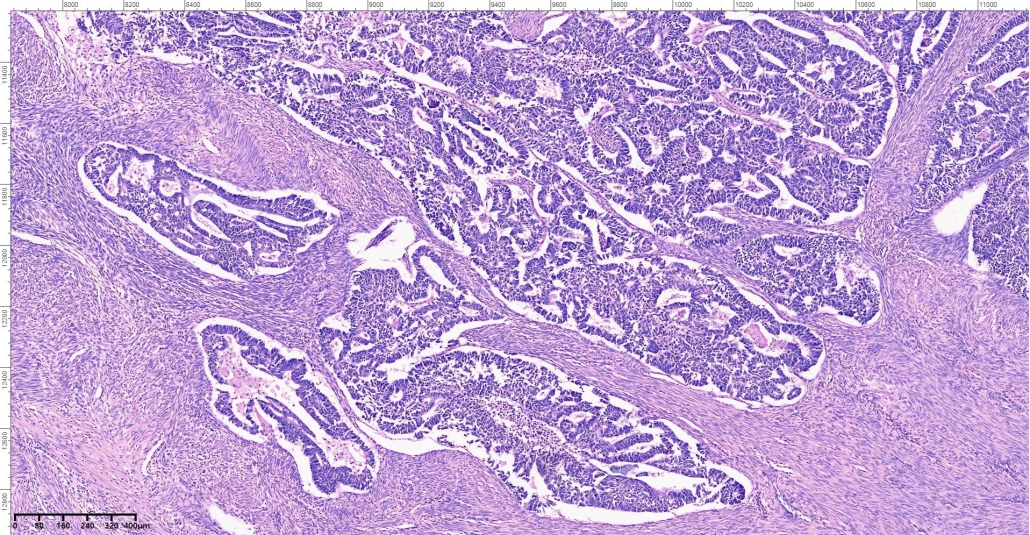

A 65-year- old female presented with vaginal bleeding. On radiological examination there was a diffuse thickening of endometrium. Patient underwent total abdominal hysterectomy and bilateral salpingo ophrectomy. On gross examination there was a grayish white mass involving the uterine cavity.